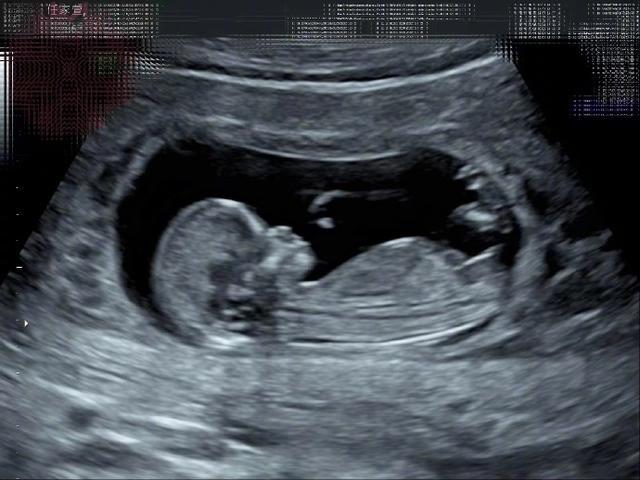

Selina宣布怀孕的微博配图。据台媒,她今年3月13日在微博、电台宣布怀孕喜讯,目前怀孕12周。Selina透露,先前熬夜跨完年觉得身体不舒服,隔几天想说测一下,立刻出现两条线,“觉得我眼花有这么严重吗?这是怎么回事?”打给男友帮忙买其他牌子的验孕棒测试,讲到激动处还一度感动哭出来,坦言当下眼泪当场喷出来,“我要当妈妈了,真的就哭了。”她还给孩子写了一首诗:“去年三月,我介绍小徐时写了首打油诗,公平起见,今年这首打油诗就送给小腰果吧!女人四一一枝花,幸运生命正萌芽,彼此珍惜同步伐,大喜大乐请吃糖。春暖花开,我的腰果也来了。”